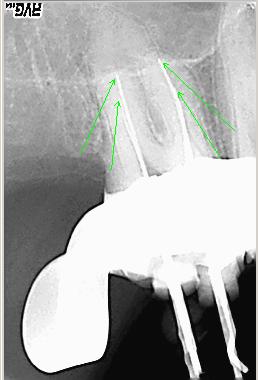

Röntgenmeßaufnahme

Röntgenmeßaufnahme nach vorgängig durchgeführter endometrischer Längenbestimmung

Bearbeitetes Röntgenbild

Bearbeitetes Röntgenbild mit Hinweis auf mögliche zusätzliche Kanalsysteme MB2 und DB2 Zahn 17 ist nicht erhaltungsfähig

Erneute Messaufnahme von MB1, MB2, DB1und DB2. Sowohl die distobuccalen wie auch die mesiobuccalen Kanalsysteme konfluieren etwa im mittleren Wurzeldrittel. Die grünen Pfeile markieren jeweils die Instrumentenspitzen